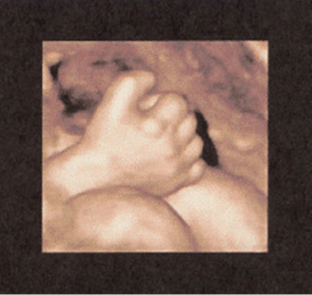

FIGURE 8–25. Three-dimensional sonogram of fingers of a fetus at 30-weeks’ gestation. (Courtesy of Philips Healthcare.)